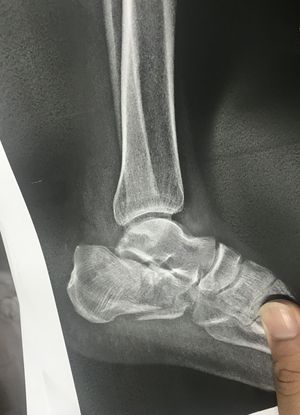

Where do you think the fraction is in this X-ray??

At the bottom of the calcaneus bone ?

Lateral view of calcaneus bone

Bottom of the calcaneus